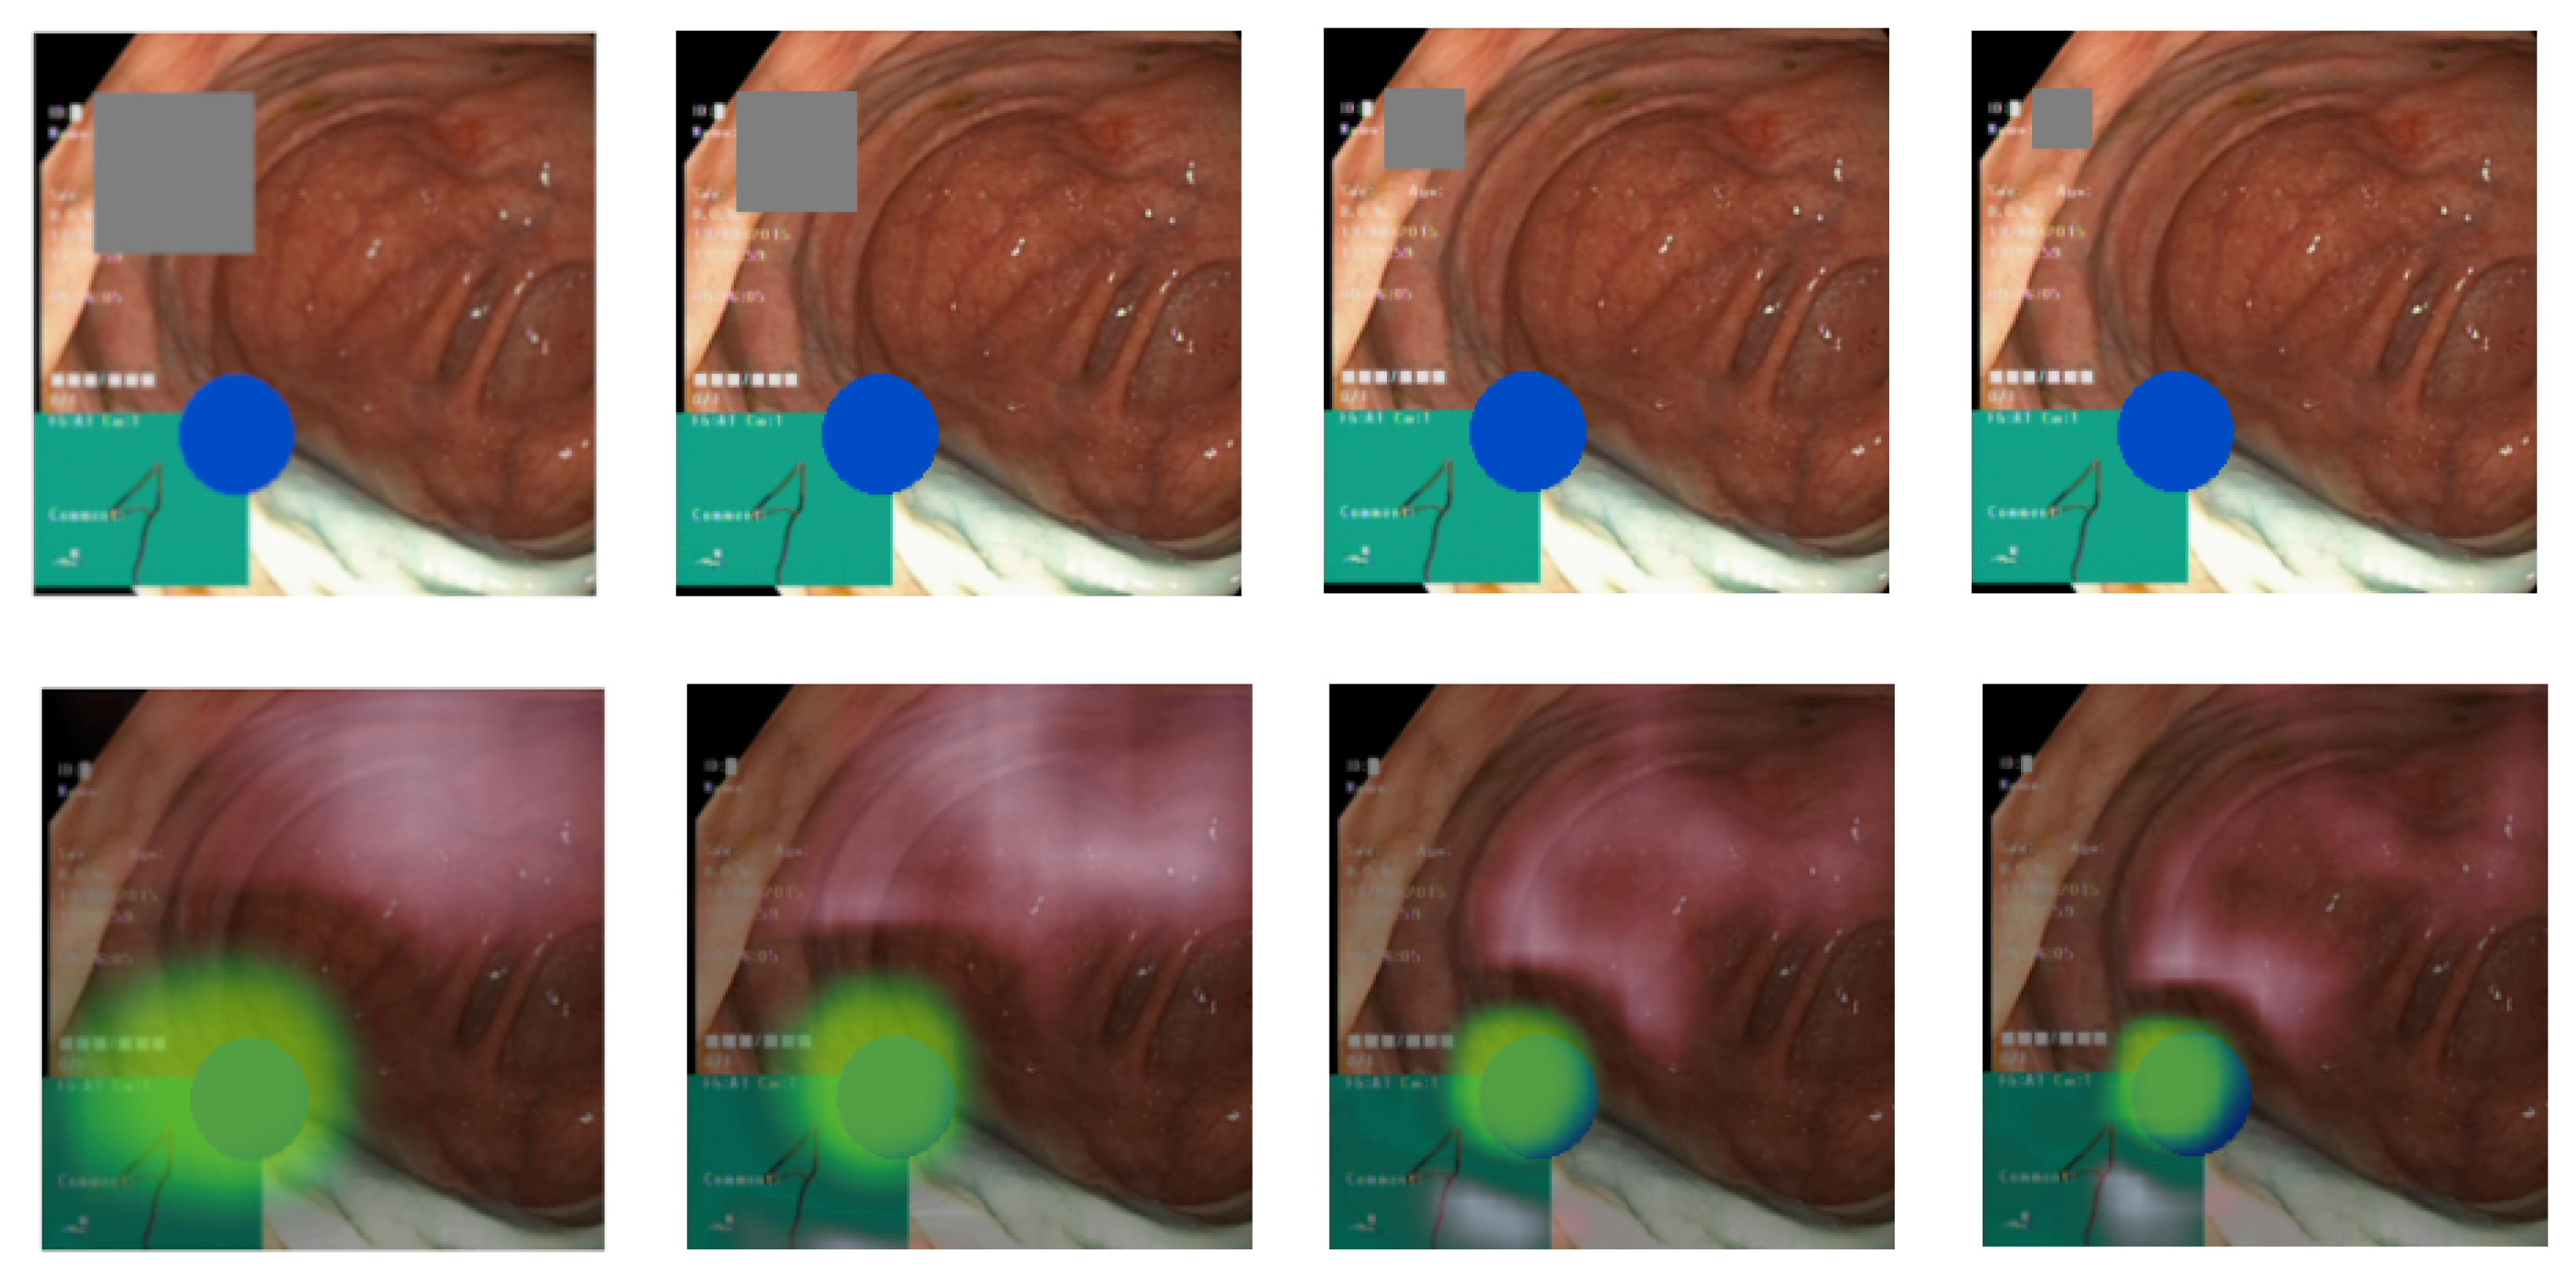

While the focus is appropriately directed, the samples in Figure 6 and Figure 7 reveal that it is slightly offset towards the top left of the pathological identifier. We believe this is likely a result of the combination of the chosen attribution method, which applies gray rectangles from the top-left to bottom-right, the selected patch size, and the classifier architecture. This conclusion is drawn from the observation that this offset is consistently present across all classes and in explanations from both Datasets A and B. Despite these weaknesses with the occlusion-based method, it performed better in our experiments than gradient-based methods. Delving deeper into the source of the offset would necessitate further research, but is beyond the focus of this paper. The focus of the paper is to demonstrate the usefulness of the suggested medical knowledge discovery framework, rather than improving existing DL, XAI, and clustering methods. The alignment with the anticipated focus and the level of detail captured also hinge on the chosen hyperparameters. Figure 8 illustrates the relationship between patch size and explanation accuracy. The top row of images presents the image with a gray patch for size reference, while the bottom row displays the corresponding explanations. Beginning on the left, the figure showcases patch sizes of 64 pixels, followed by 48, 32, and concluding with 24 pixels. The first patch, approximately 150% the size of the ellipse, results in significant attribution to areas outside the ellipse. The subsequent patch, roughly equivalent in size to the ellipse, still attributes large areas outside of the ellipse, albeit to a lesser degree than the preceding patch. Shrinking the patch to 75% of the ellipse’s size yields a more precise attribution area. Further diminishing the patch size to 50% of the ellipse’s size reduces the extraneous attribution but also omits some accurate attribution from the ellipse. We observe that the explanations are profoundly influenced by the chosen patch size. As patch size enlarges, recall surges, and as it diminishes, precision intensifies. This presents a balancing act we must consider.

Figure 8. Visualization of how the patch size affects the explanation. (Top row) The gray square shows the patch size and the blue ellipses the pathology. (Bottom row) The green overlay shows the resulting explanation using the patch size in the image above.